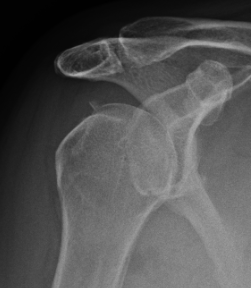

Type IA: Anterior glenoid rim fracture

Xray / CT